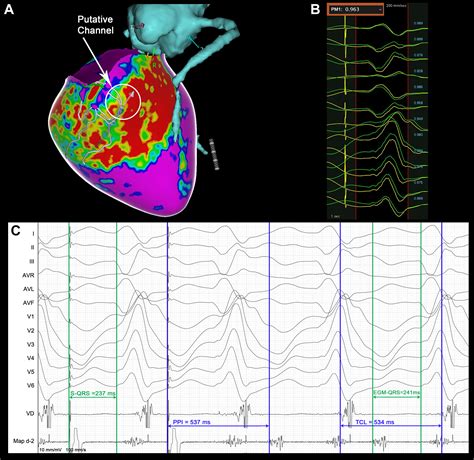

3. Mapping the Heart: The catheter is used to map the electrical activity of the heart. This helps the cardiologist identify the specific areas causing the abnormal heart rhythm.

4. Ablation: Once the problematic areas are identified, the catheter delivers radiofrequency energy or cryoenergy to destroy the abnormal tissue. This process is carefully monitored to ensure the correct areas are targeted.